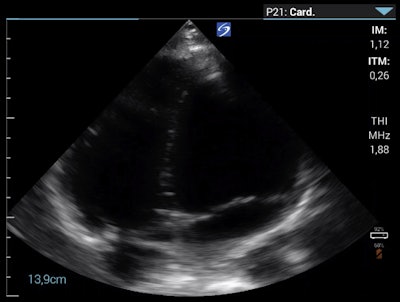

To investigate pulmonary embolism (PE) as a potential cause of the clinical deterioration, the researchers performed point-of-care echocardiography (parasternal long axis, parasternal short axis, and apical four-chamber view). These views showed a slightly enlarged right ventricle/left ventricle ratio greater than 0.6, which allowed them to exclude a large, central PE.

Wipplinger said that although they could not exclude peripheral PE, the patient did not have typical symptoms, such as chest pain or a cough, which made them question peripheral PE as a differential diagnosis. They interpreted the right ventricle enlargement as an indirect sign of pulmonary hypertension that was most consistent with HAPE.